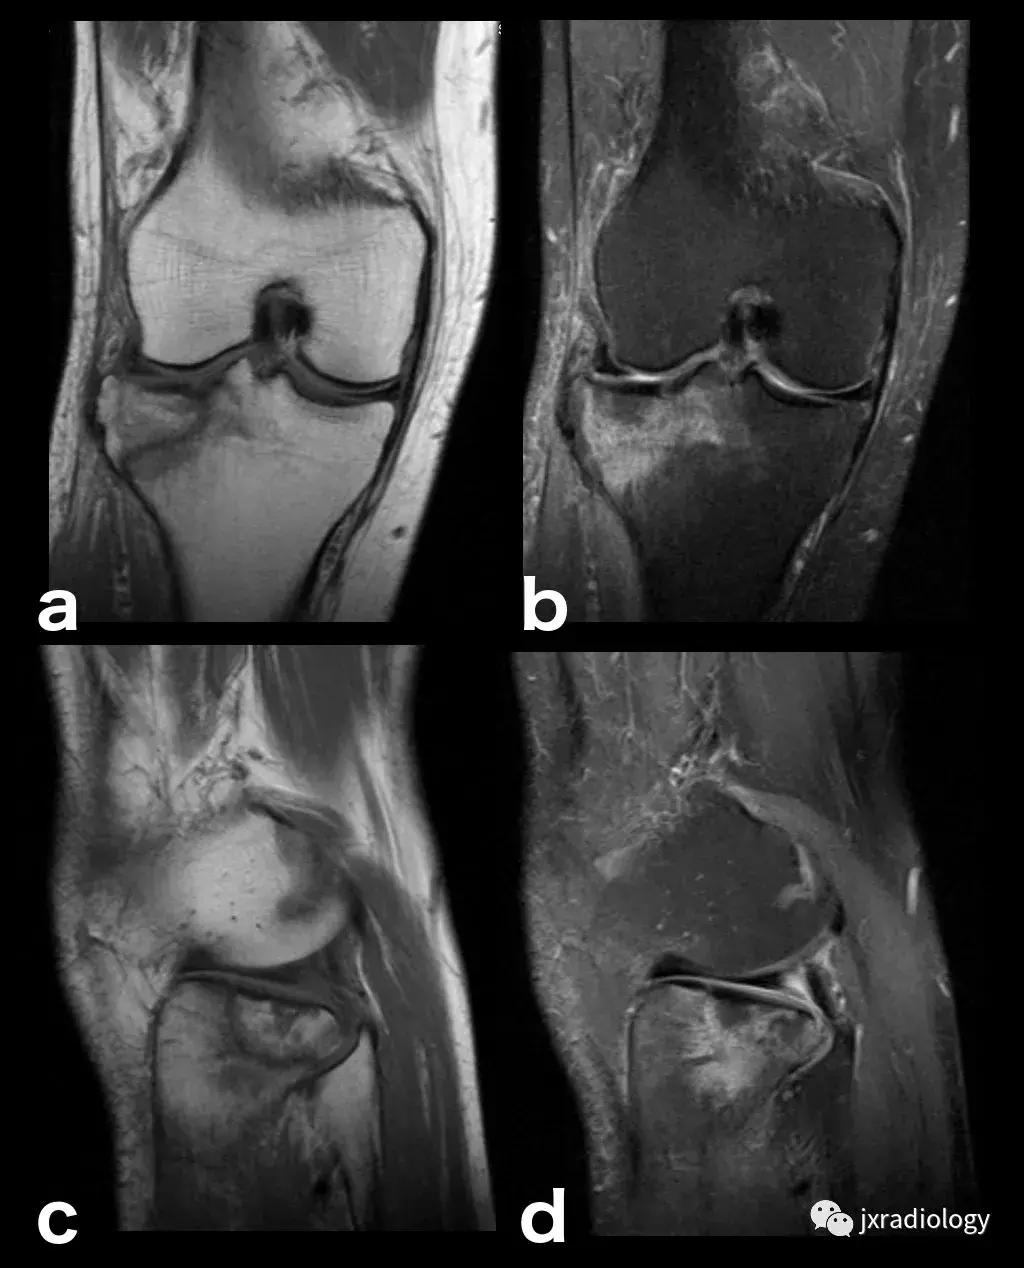

图8:创伤性骨髓水肿,髌骨脱位的典型病例:青年人,髌骨一过性脱位和挫伤的横断面(a,b,c),冠状面(d,e)和矢状面(f)的PD-FS-WI图像 :股骨外侧髁的前外侧和髌骨下内侧的故事水肿。对于进行运动的青少年或年轻人来说,在弯曲时需要膝盖扭转运动的情况更为常见。如该患者患有髌骨骨软骨损伤(*)和内侧髌股韧带(MPFL)撕裂(箭头)。